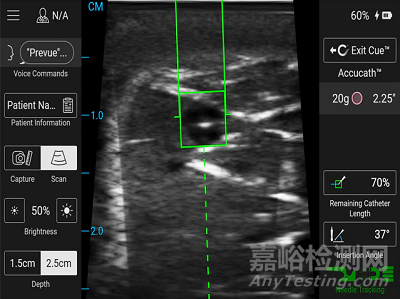

BD預(yù)覽版™ II血管接入系統(tǒng)可以支持集成BD Cue的訓(xùn)練™ 針頭跟蹤技術(shù),一種針頭軌跡的虛擬屏幕顯示,使臨床醫(yī)生能夠查看正確的針頭對(duì)齊和靜脈引導(dǎo)。

在護(hù)士報(bào)告使用BD提示™ 模擬超聲引導(dǎo)放置過(guò)程中的針頭跟蹤軟件比單獨(dú)的超聲更容易,也更可取。

BD Prevue™ II血管接入系統(tǒng)具有創(chuàng)新的血管評(píng)估工具,可幫助臨床醫(yī)生根據(jù)插入位置和角度選擇合適的導(dǎo)管長(zhǎng)度和規(guī)格,以便他們每次都能做出明智的決定。